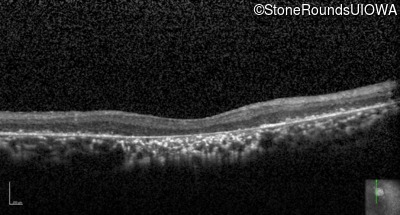

Optical Coherence Tomography - Right - Count Fingers

Exemplar / OCT Stack

Optical Coherence Tomography - Left - Count Fingers